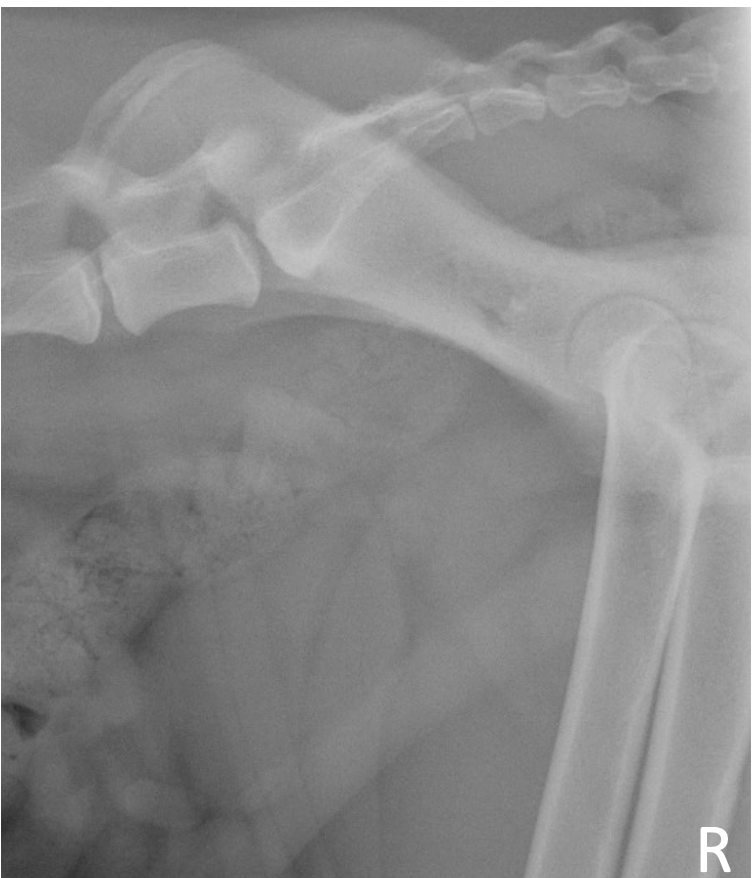

What is shown in this image?

A

prostatomegaly

-occupies ~ 90% of pelvic inlet diameter

-irregular, ill-defined margins